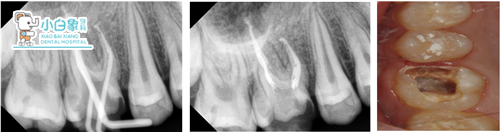

b.16根管治疗+龈切+高嵌体修复

治疗过程:a.16去腐质,揭髓顶,拔髓未见,冲洗,隔湿干燥,封木榴油。一周复诊根充,局麻下切龈,制备牙体,扫像,设计,研磨,上釉,粘结,调合。

嵌体粘结

一周复查